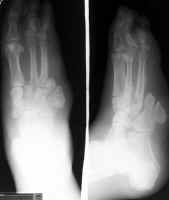

The images to the left show a proximal

transmetatarsal amputation through digits 4 and 5.